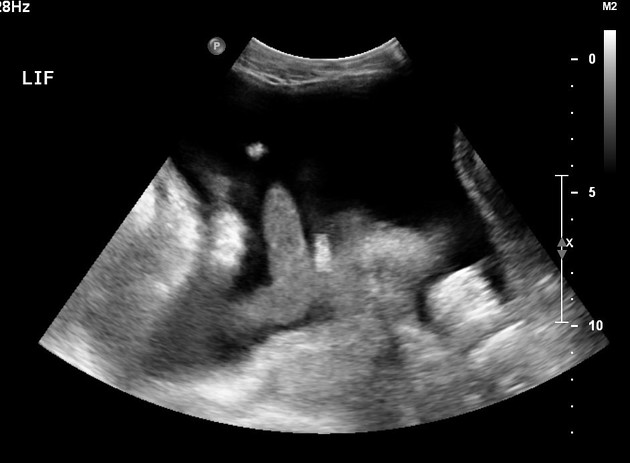

Case 3: Nephrostomy on Apixaban

Scenario: 70M with obstructing stone, febrile, pyonephrosis. On apixaban for DVT (CrCl 40).

Scenario: 70M with obstructing stone, febrile, pyonephrosis. On apixaban for DVT.

Plan: - Emergent nephrostomy needed

• Hold apixaban, but proceed with procedure

• Reversal options: Andexanet alfa (factor Xa inhibitor) or PCC if bleeding occurs

Evidence: SIR guidelines suggest holding DOACs for high‑risk procedures, but in emergencies, proceed with caution. Reversal agents can be considered if bleeding occurs.

Take‑home: In emergencies, prioritize patient stability. Hold DOACs if possible, but don’t delay critical interventions. Know your reversal options.